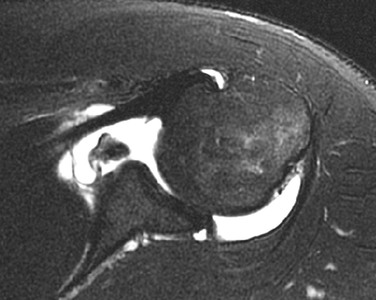

Although conventional MRI is established as the imaging modality of choice in the evaluation of shoulder impingement syndrome, MRA is accepted as the method of choice for the evaluation of glenohumeral instability.22,23 Many of the lesions associated with instability are subtle and may undergo partial healing. This situation, coupled with the fact that the normal anatomic structures of the shoulder lie in close proximity, can make the diagnosis of these lesions difficult even with high-quality conventional MRI.58-62 MRA, on the other hand, is performed by distending the joint with fluid (saline solution or dilute gadolinium), which more accurately depicts subtle labral tears, cartilage and ligamentous abnormalities, and partial-thickness tears of the undersurface of the rotator cuff. The standard injection technique for MRA of the shoulder is described in previous sections. About 12 to 14 mL of gadolinium diluted 1 : 200 with normal saline solution or 1% lidocaine is injected. Imaging protocols vary, but a standard set of imaging sequences typically includes T1-weighted images with frequency-selective fat saturation in the axial, oblique sagittal, and oblique coronal planes. The T1-weighted images have a high signal/noise ratio, resulting in the anatomic detail that is critical in detecting the subtle lesions associated with glenohumeral instability. A T2-weighted sequence performed in the oblique coronal plane is the most important sequence for depicting rotator cuff abnormalities. A T2-weighted sequence may also be helpful in detecting other pathologic processes, such as a paralabral cyst or bone marrow edema (Fig. 44-7, A and B). The ABER view may be added to the standard imaging protocol for any patient thought to have an anterior labral pathologic process.54

MRI and MRA are the main imaging modalities used in the evaluation of a patient with glenohumeral instability.22,23 Even with 3-tesla magnets, MRA demonstrated superior sensitivity compared with routine MRI in a study of 150 consecutive examinations for detecting SLAP lesions and labral tears.138 Joint distention with fluid outlines and separates the normal anatomic structures, allowing more accurate depiction of subtle lesions (Fig. 44-36). CT imaging with sagittal and coronal reconstructions remains the study of choice for detecting and depicting the size and location of a fracture fragment of the anteroinferior glenoid rim (see Fig. 44-4), which can be useful in presurgical planning in patients with large osseous Bankart lesions. As previously stated, MDCT arthrography is accurate for detecting instability lesions and very useful for patients who cannot undergo MRA or lack access to MRI services. The addition of MRI stress views, such as the ABER view (see Fig. 44-37, C), may improve visualization of a nondisplaced tear in the anterior inferior labrum.54